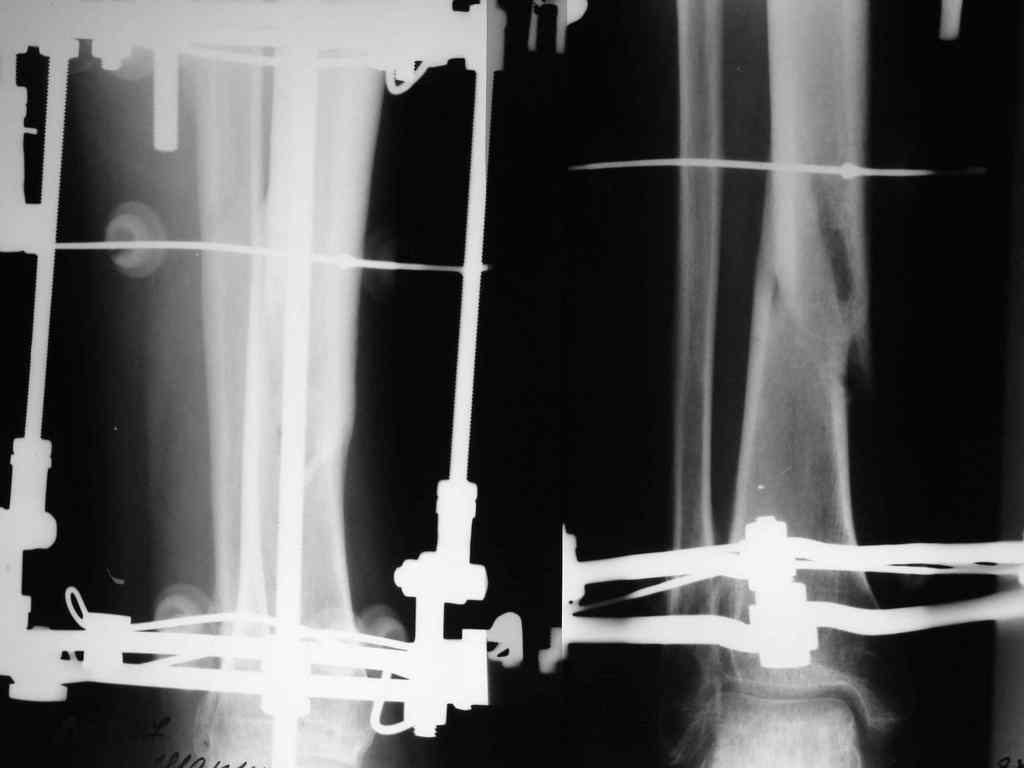

И ещё: Имеется у нас пациент с переломом обеих костей левой голени. Перелому 13 месяцев. После 6-ти месяцев фиксации в гипсе был наложен аппарат Илизарова.

После коррекции длинны и оси конечности аппарат стабилизирован. В аппарате 7 месяцев. Последние снимки прилагаются. Консультирован на консультативном приёме в УНИИТО. Рекомендовано ослабить аппарат на 20 мм.(!) и ходить с полной нагрузкой на конечность. Убедительная просьба рассмотреть вариант лечения данного пациента в условиях УНИИТО (МОС блокируемым стержнем), т.к. пока не располагаем набором развёрток.